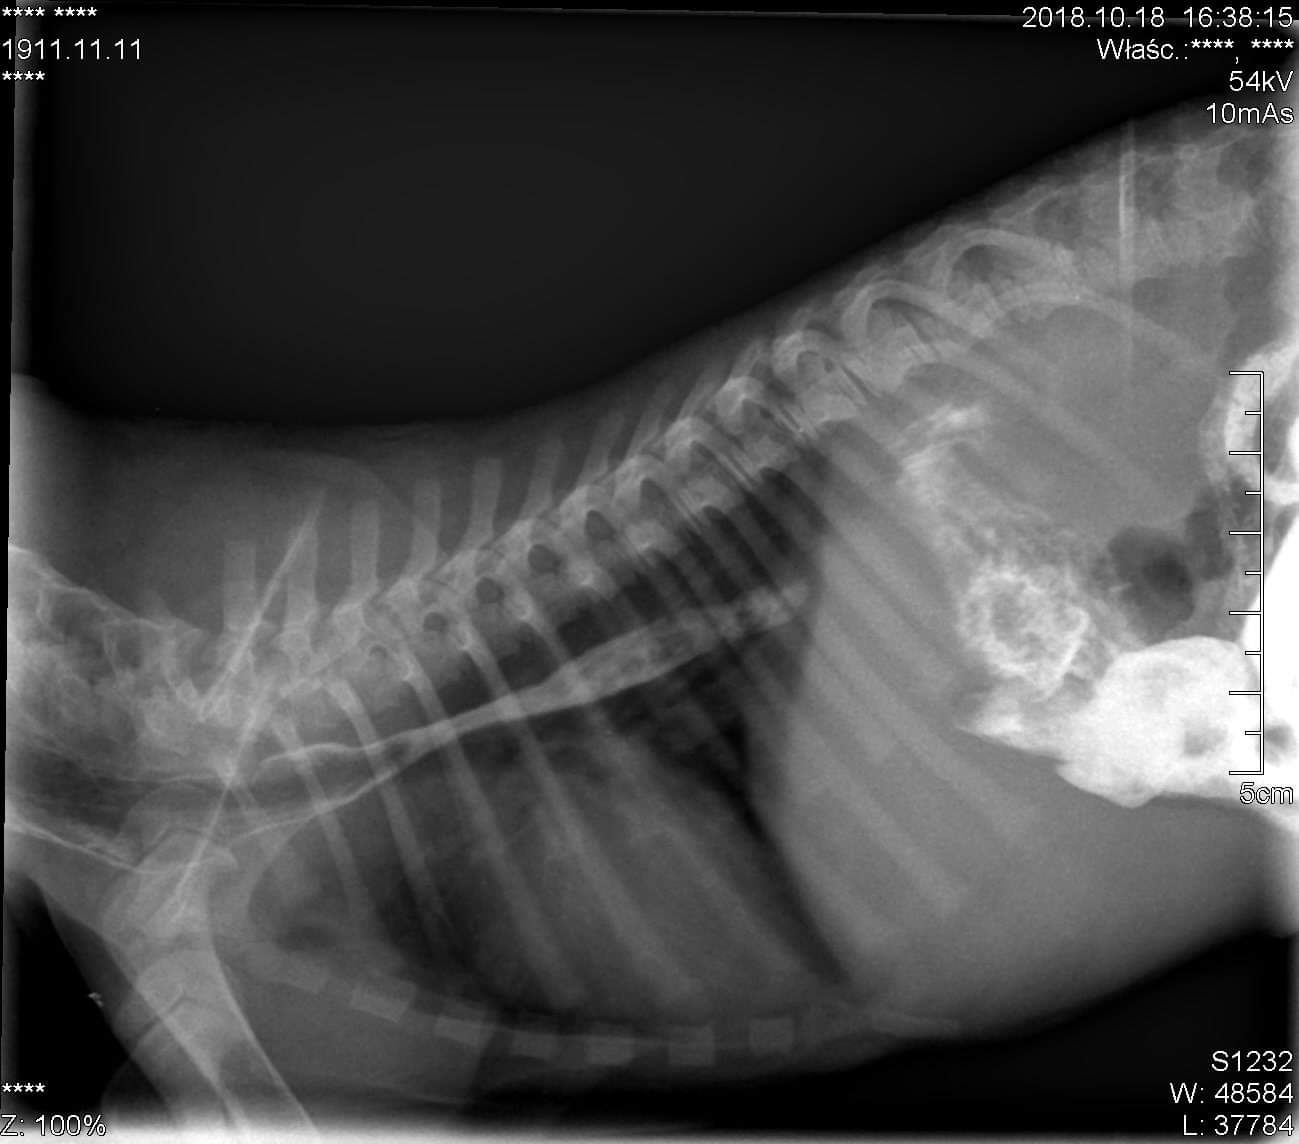

Mały murzynek został porzucony przez właściciela, jest pod opieką dobrych ludzi i lekarza, ale bez drogiej operacji jego życie jest dla niego uciążliwe i kto wie jak długie, a mianowicie maluch potrzebuje przede wszystkim postawienia jednoznacznej diagnozy, gdyż waha się ona między PRZETRWAŁYM PRZEWODEM TĘTNICZYM BOTALLA a PRZETRWAŁYM PRAWYM ŁUKIEM AORTY Z UCHYŁKIEM PRZEŁYKU. Nasza mała pociecha ma problem z jedzeniem, wymiotuje, przez co jest wychudzony, a w gardle rośnie ,,gula,, na załączonym zdjęciu RTG (

) widać ucisk który blokuje cały proces trawienia malucha dlatego też bardziej prawdopodobną diagnozą jest ŁUK AORTY, piesek każdego dnia się męczy więc dajmy mu szansę na normalne życie tym bardziej, że to dopiero maluch, jest wesoły, che się bawić, lecz przez chorobę po chwili się męczy i nie ma siły, wymaga ona zdiagnozowania oraz operacji z pobytem w szpitalu, pomóżmy mu! Ja wraz z jego obecnymi opiekunami zajmujemy się nim najlepiej jak potrafimy, jesteśmy technikami weterynarii pod opieką lekarza weterynarii w Nysie, ale tylko z waszą pomocą zdołamy mu pomóc i dać nowe życie!